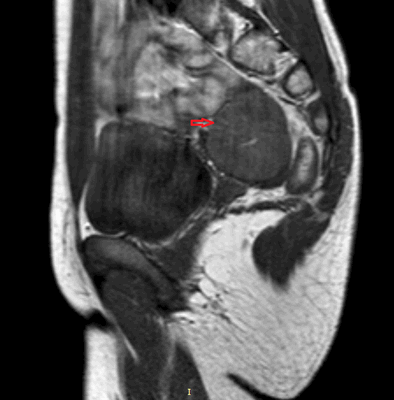

Рисунок 3. - тератома яичника а -УЗИ, б — МРТ.

- КТ (расшифровка: компьютерная томография), МРТ (расшифровка: магнитно-резонансная томография), ПЭТ-КТ (расшифровка: позитронно-эмиссионная томография, совмещенная с КТ). Эти обследования необходимы, чтобы рассмотреть структуры организма послойно и визуализировать опухоль. Они показывают, как сильно распространен патологический опухолевый процесс на находящиеся рядом ткани и органы, есть ли поражение костей. КТ - это самый чувствительный метод для обнаружения метастазов в легких. Проведение МРТ и КТ головного мозга необходимо, чтобы обнаружить и визуализировать герминогенные новообразования эпифиза.